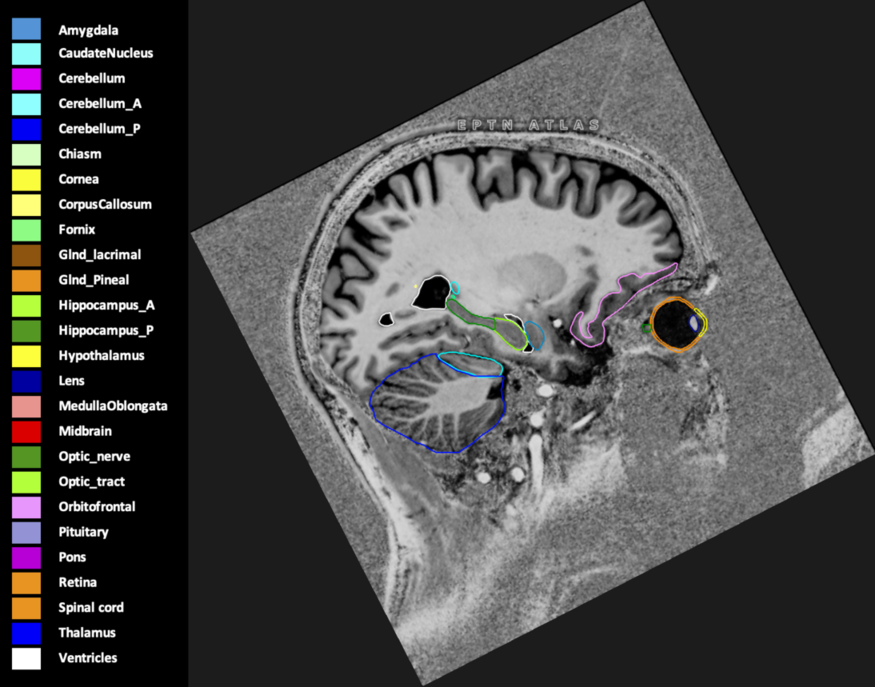

Included are all OARs known to be relevant for radiation-induced toxicity in neuro-oncology: brain, brainstem (midbrain, pons, medulla oblongata), chiasm, cerebellum (anterior & posterior), cochlea, cornea, hippocampus (anterior & posterior), hypothalamus, lens, lacrimal gland, optic nerve, pituitary, skin, and vestibular & semicircular canals. To further facilitate research on cognition, vision and radiological changes after irradiation of the brain, potential clinically-relevant OARs are included: amygdala, caudate nucleus, cerebellum (anterior & posterior), corpus callosum, fornix, macula, optic tract, orbitofrontal cortex, periventricular space (PVS), pineal gland, and thalamus.

Three-dimensional delineation of the 25 consensus OARs for neuro-oncology are shown on CT (WW/WL 120/40, 3000/600), 3T MR images, (T1Gd, T2FLAIR 1mm) and 7T MR (MP2RAGE 0.7 mm). All are presented in transversal, sagittal and coronal view.